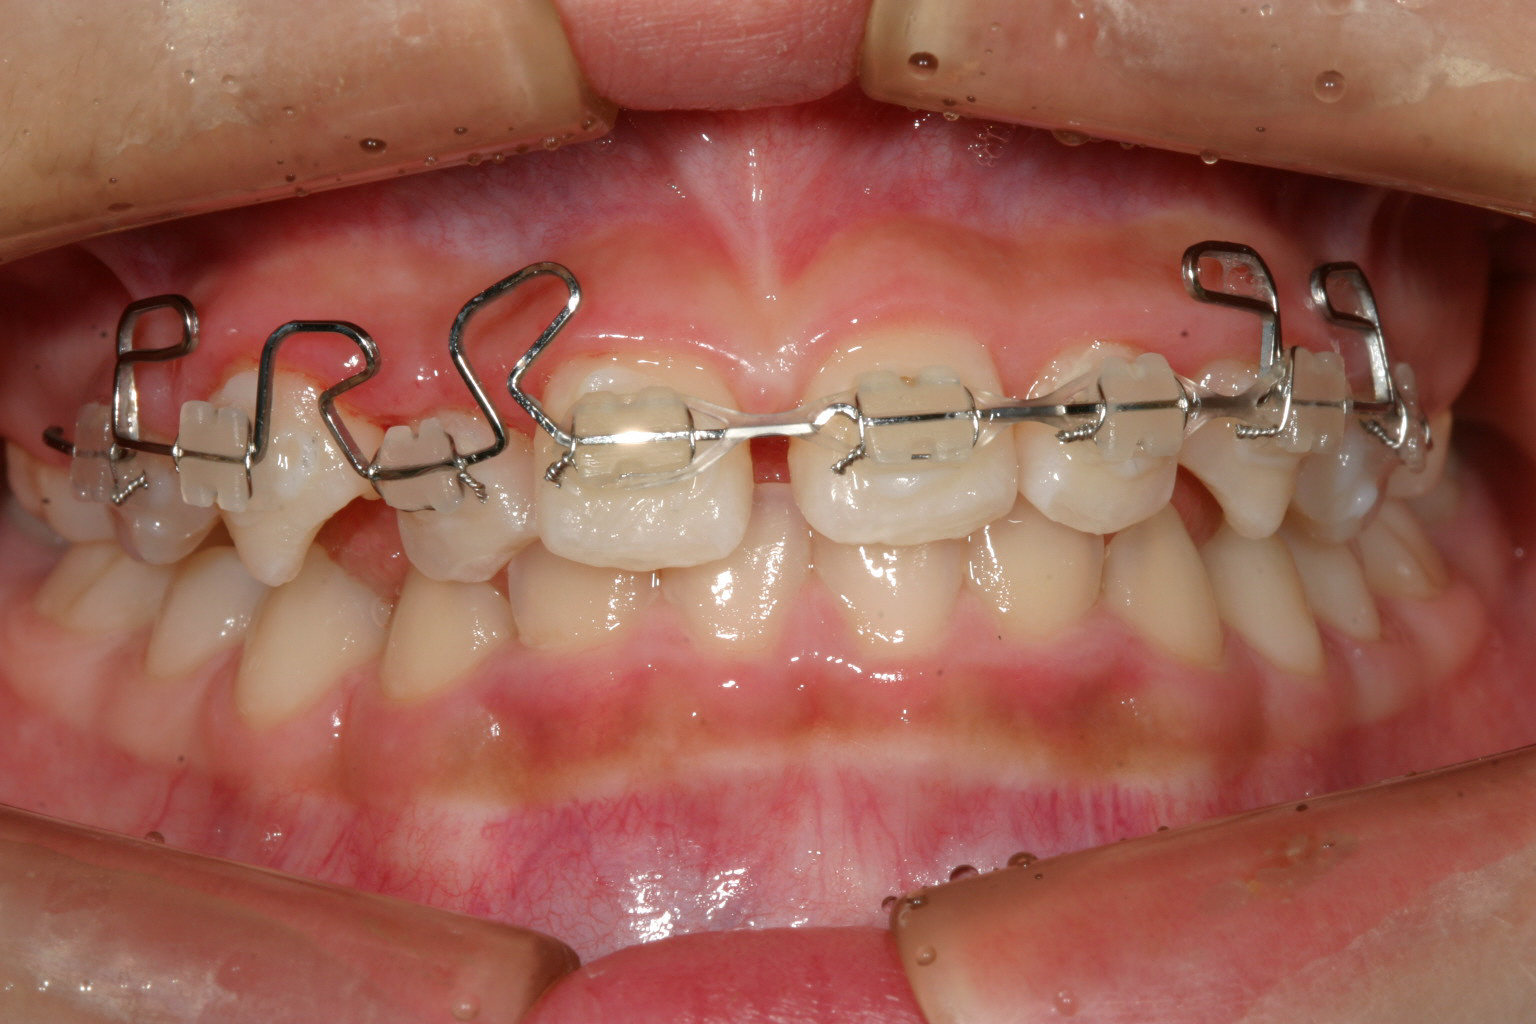

マルチループワイヤー

ワイヤー張って2ヵ月です。